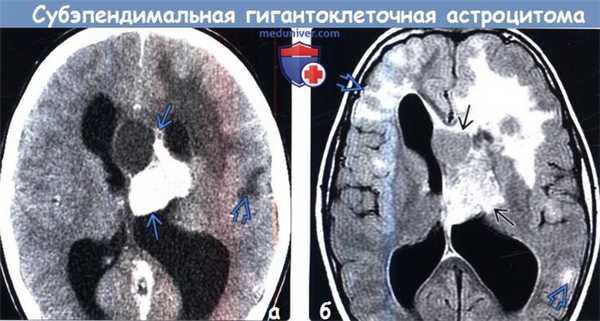

Диагностика субэпендимальной гигантоклеточной астроцитомы по КТ, МРТ

(а) КT с контрастированием, аксиальный срез: у пациента с ТСК определяется крупное частично кальцифицированное объемное образование, обтурирующее отверстие Монро. Обратите внимание на гиподенсный участок поражения в подлежащем кортикальному туберсу белом веществе.

(б) MPT, FLAIR, аксиальный срез: у того же пациента определяется, что выявленное образование имеет неоднородно гиперинтенсивный сигнал. Обратите внимание на кортикальные туберсы и очаги гиперинтенсивного сигнала, расположенные в субкортикальном белом веществе. При операции была выявлена СГКА.

2. КТ при субэпендимальной гигантоклеточной астроцитоме:

• Бесконтрастная КТ:

о Плотность от гипо- до изоденсной; гетерогенная структура о Наличие Са++ вариабельно

о Гидроцефалия

• КТ с контрастированием:

о Интенсивное, гетерогенное накопление контраста

о Выявление роста образования предполагает субэпендимальную гигантоклеточную астроцитому (СГКА)

о Изначально опухоль обычно имеет размеры 1 см